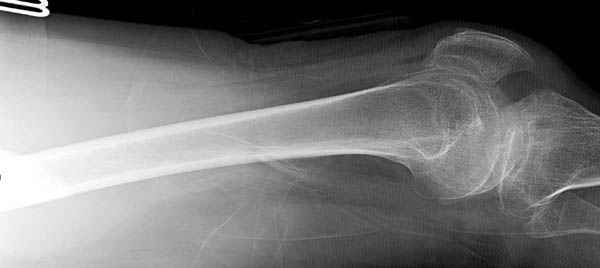

Среди русскоговорящих коллег Ортофорум стал одним из мест, где многие из нас черпают знания для решения своих ежедневных проблем в виде практических советов и обмена опытом. Кроме таких советов, Ортофорум стал источником новых познаний среди ортопедов, особенно по редко встречающимся состояниям в ортопедии. Продолжая традицию, я хотел бы представить редко встречающий случай перелома бедра у больного с гемофилией. Больному 42, гемофилия типа А, из истории упал с высоты около 1,5 метра, переправлен из другой больницы. По происхождению мексиканец, 10 лет назад по поводу артроза пр. коленного сустава в Мексике сделано протезирование, которое закончилось ампутацией выше коленного сустава. При поступлении бедро напряженное, сосудистых и неврологических расстройств нет. На рентгенограмме оскольчатый перелом бедра с вовлечением проксимальной спирали в шейку бедра. Хотели бы знать тактику ведения подобных больных и на что надо обратить внимание? Djoldas Kuldjanov, MD Department of Orthopedic Surgery St. Louis University Medical Center

Учитывая, что случай ургентный, больной поступил вечером, не стали делать вытяжение и срочно провели операцию по фиксации перелома бедра антеградным штифтом Versa Nail от DePuy.